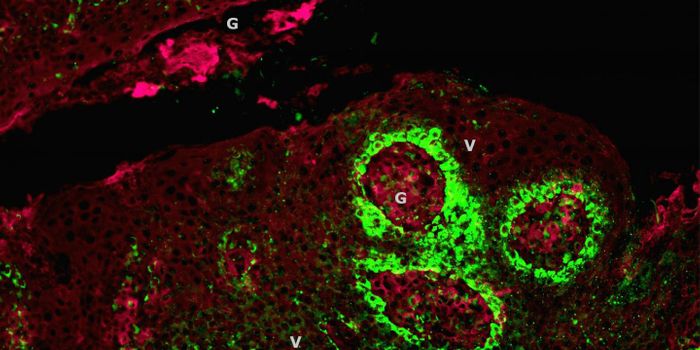

JUN 18, 2015CancerAccording to the National Cancer Institute, prostate cancer is the most common cancer in men in the United States, after ...